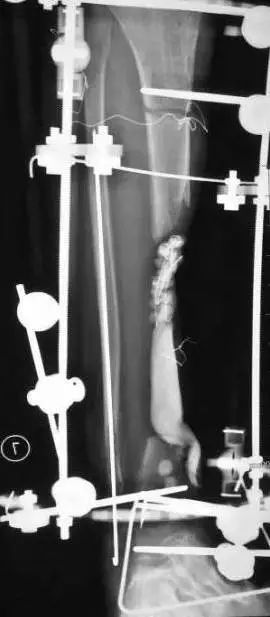

(网友提供)最后的病例是伤后40天由外地转来。开放骨折外固定架固定,骨坏死外露,用连珠和双氧水冲洗。入院时还存在足下垂,腓神经损伤、胫后动脉损伤。

Tips

• 接收该患者后第一次手术  清除病灶去除死骨27cm

• 抗生素骨水泥填塞。远端整块水泥包裹外露骨质,近端连珠以便骨搬移

• 钢丝克氏针张力牵拉皮肤,缩小创面

• 5天后下地部分负重走路

• 联合骨牵引纠正足下垂,5天后足下垂纠正后去除跟骨骨牵引针,保留胫跖骨牵引维持足于功能位。

• 而后行骨搬移、半开放植骨(如下)

• 第一次的骨水泥于80天后去除,行半开放植骨(植骨表面覆盖抗生素骨水泥)

• 因为有皮肤缺损,用骨水泥做成瓦片闭合伤口=半开放植骨

• 自体优质松质骨(如图)

• 皮肤采用了钢丝牵张闭合

• 骨搬移+半开放植骨=治疗缺损

• 植骨后一个月去除瓦片骨水泥,创面新鲜

• 钢丝克氏针张力闭合伤口加游离植皮

• 继续骨搬移

• 修整

• 入院6个月腓总神经恢复,胫前动脉再通

• 总的治疗过程2年基本完全康复

1、双氧水不要用于急症手术冲洗伤口,也不要用于换药2、应用骨水泥时做骨搬移有阻挡作用3、骨搬移过程中,持续的外伤刺激修复中血管扩张增生,原来闭塞的血管再通或周围的动脉扩张。4、单边外固定架加半环架搬移基  本不影响关节活动5、皮肤牵张法的基本使用方法是 皮内置入细克氏针后钢丝缝合。欢迎指正,谢谢大家。